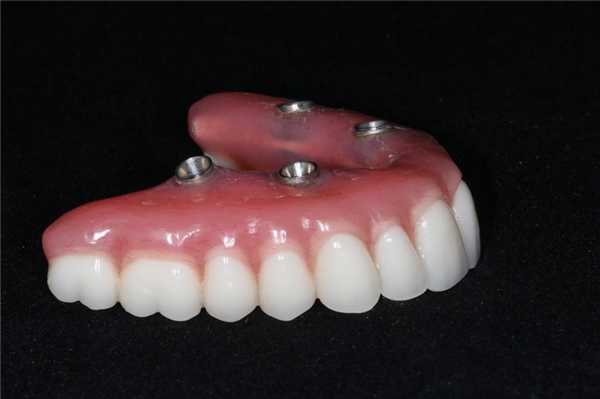

Временный протез функционировал на протяжении 6 месяцев для полной адаптации пациента к внешнему эстетическому виду и новым окклюзионным соотношениям. Окончательная протетическая конструкция состояла из титанового каркаса, покрытого десневым композитом Gradia (GC America), и металлокерамических коронок, зафиксированных поверх титанового базиса (фото 18). Окончательный результат реставрации виден на фото 19.

Фото 18. Вид окончательного протеза через год после первичного вмешательства.